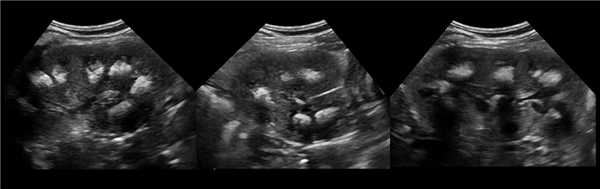

• Исследование 8 режиме серой шкалы:

о Нормальный контур почки

о Обычно изоэхогенно по отношению к корковому веществу

о Цветовое и энергетическое допплеровское картирование позволяет визуализировать поток, идентичный корковому веществу

о Разделение центральных эхосигналов

(Слева) УЗИ, продольная плоскость сканирования: гипоэхогенное «объемное образование» в центре, которое выступает в почечную лоханку.

(Справа) КТ с контрастированием, аксиальная проекция: у этого же пациента установлено, что «объемное образование» — это нормальное корковое вещество почки, которое инвагинирует в почечную лоханку между чашечками верхнего полюса и меж полюсной областью почки. Обратите внимание на нормальный внешний контур почки. Бертиниевы колонны чаще всего выявляют с одной стороны и слева, как в данном случае: в 18% случаев они могут быть двусторонними.

Наиболее частой причиной псевдоопухоли была "гипертрофия" столбов Бертена или "перемычки" паренхимы почек - у 153 (86,4%) пациентов (рис. 3 г-е). "Перемычки" паренхимы были отмечены не только при различных удвоениях чашечно-лоханочных систем почек, но и при различных их сращениях и незавершенных поворотах почек.

Рис. 3 (г-е). Псевдоопухоль гипертрофия Бертена (неполная "перемычка" паренхимы) в среднем отделе правой почки.

г) Эхограмма.

д) Экскреторная урограмма.

е) КТ с контрастным усилением.